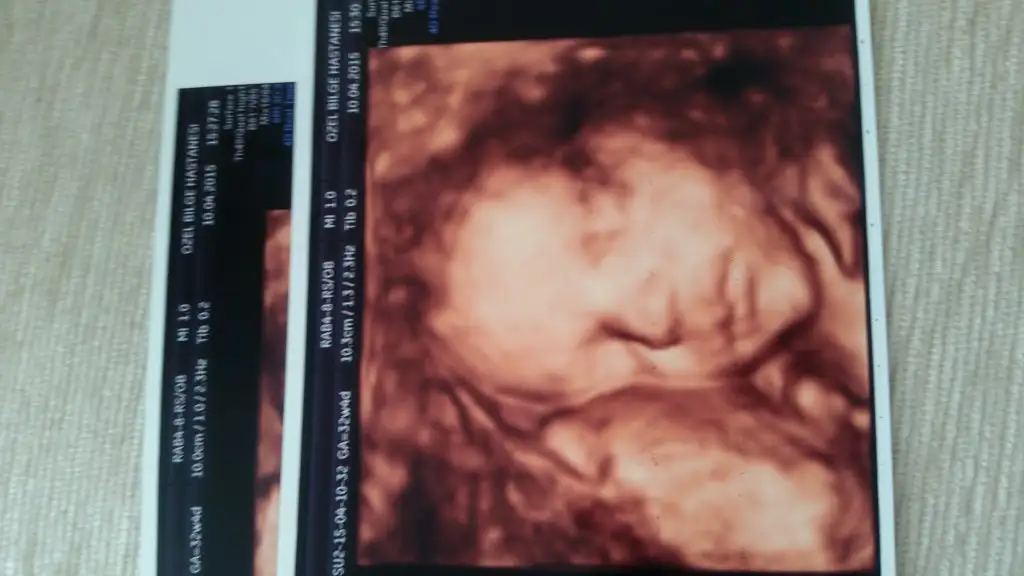

Maşallah yerimm seni bennn oyş kurban olduklarım32+4 de biiizzz:)